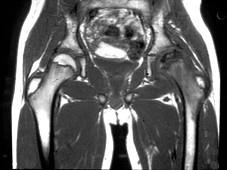

问题 男,6岁,左髋部疼痛、乏力、跛行,请结合MRI检查,选出最可能的诊断 ( )

选项 A、骨囊肿 B、软骨肉瘤 C、股骨头骨骺缺血坏死 D、骨肉瘤 E、髋关节结核

答案 C